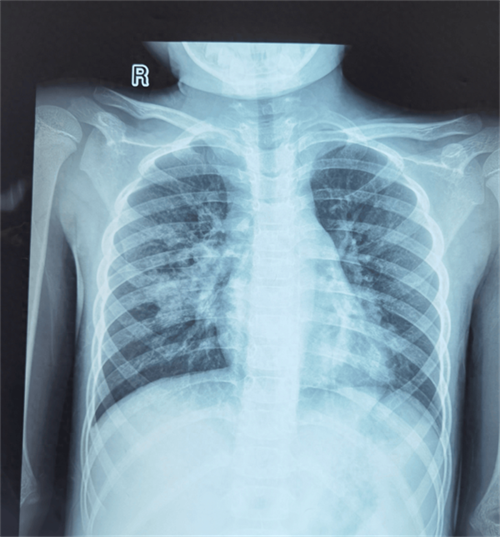

目前,支原体肺炎的诊断主要依靠支原体抗体检查和血清冷凝集试验以及鼻咽拭子的核酸检测。影像学表现是临床判断病情严重程度和评估预后的主要依据之一,肺炎支原体肺炎早期胸片或胸部CT主要表现为支气管血管周围纹理增粗、增多、支气管壁增厚,可有磨玻璃影、“树芽征”、小叶间隔增厚、网格影等,再结合上述检测即可作出诊断。

下面展示的是一组重症肺炎患儿经气管镜灌洗的前后变化,不难看出,灌洗后的肺部炎症,较之前明显吸收。

气管镜灌洗前